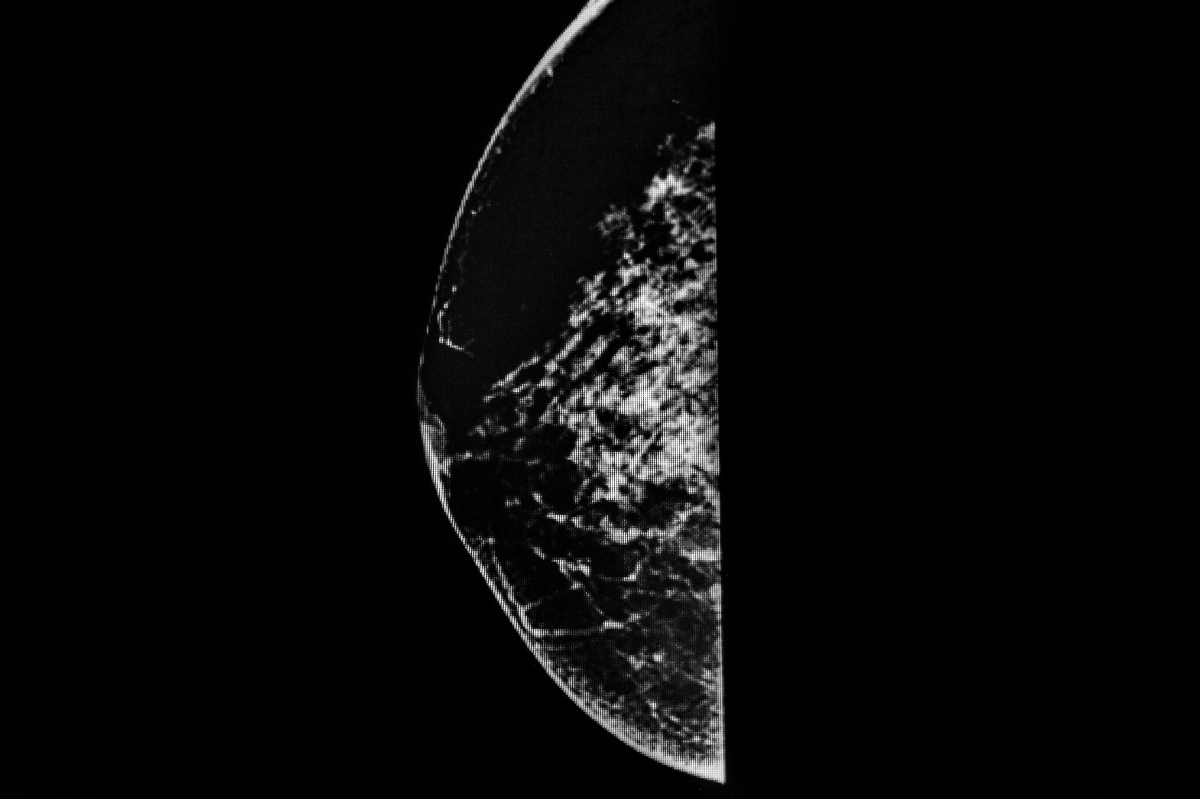

A mammogram is an X-ray image of your breast. This exam is used to diagnose and detect breast disease. If you have a lump, pain, or nipple discharge from your breasts, your physician might require this test.

Traditional mammograms can produce two-dimensional images of your breast. While a 3D mammogram, which is newer and more advanced, can create three-dimensional images.

A mammogram is done in a special X-ray machine. Your breasts will be placed on a plate before another one is firmly pressed on your breast from above. This pair of plates will hold your breast still, so a clear X-ray image can be produced. Afterward, the steps will be repeated to produce a side view image of your breast.

Your breasts must be compressed to even it out. This way, the X-rays can penetrate the breast tissue. It also prevents blurring caused by movement, so you don’t have to repeat the exam. Do your best to stand still and hold your breath during the procedure.